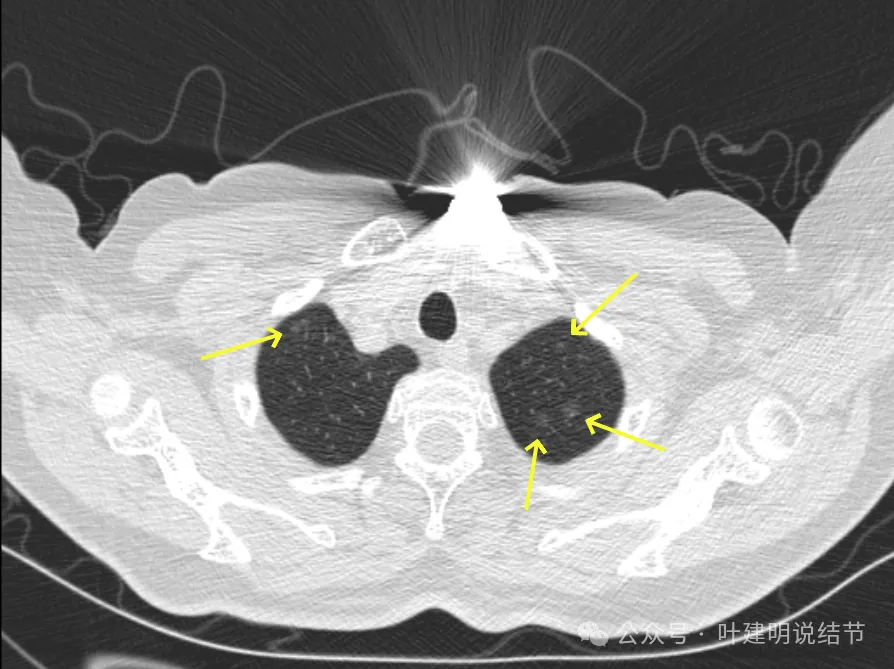

病灶7-9:右肺上叶淡磨玻璃结节,轮廓较清。

病灶10:右侧胸膜下淡磨玻璃结节,轮廓较清。

病灶11-14:两肺淡磨玻璃结节,轮廓较清。